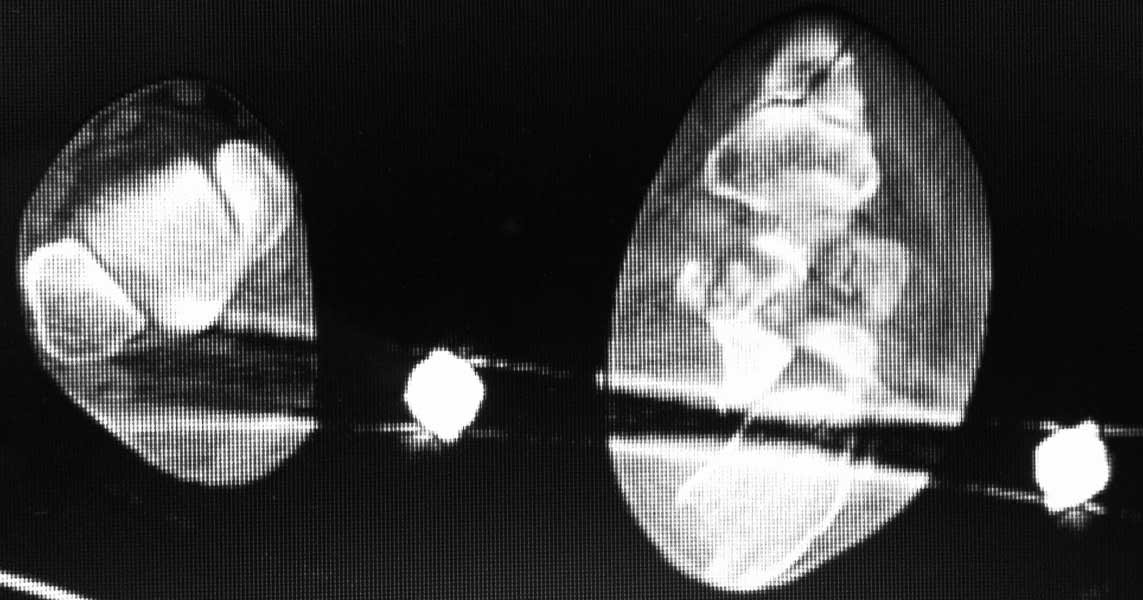

Re: Перелом пяточной кости - ваше мнение?

послал Михаил Горохов 09 Октябрь 2011, 11:12

КТ